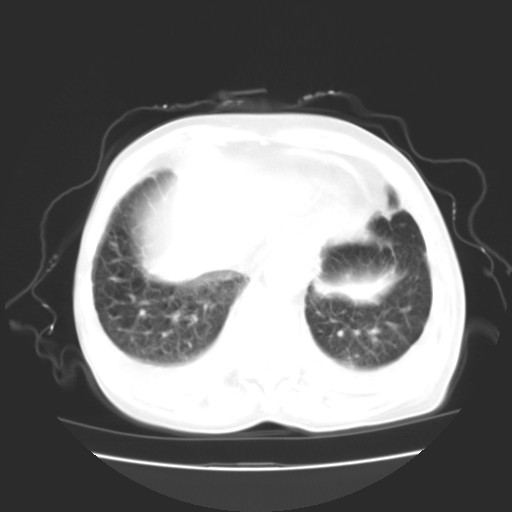

女70y乳腺ca(针吸活检)

多部位转移瘤的诊断可以肯定,我的疑问是:双肺对称高密度影及胸水是否为心衰肺水肿,病人体虚弱,不好意思图象传的乱![em9]

肺部病变为淋巴转移,肝脏转移,及局部淋巴转移。胸水可能为淋巴回流受阻(血性的考虑胸膜转移)

1)左侧乳腺癌并左侧腋窝及纵隔淋巴结转移,两肺淋巴道转移(癌性淋巴管炎),肝脏多发性转移。2)双侧胸腔积液。3)慢性胆囊炎。

癌性淋巴管炎,胸膜转移.肝内转移,纵隔及腋窝淋巴结转移

2、左腋窝、纵隔淋巴结肿大(转移性);

3、双肺癌性淋巴管炎;

4、双侧胸腔积液(考虑淋巴回流障碍所致);